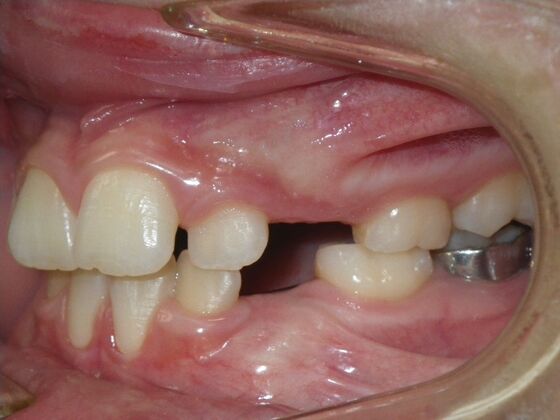

Patient presented with mixed dentition and mild deep overbite, excessive overjet,and rotated lower incisors. She also had a lower bilateral lingual retainer, preventing lower molars from coming forward. She was treated with utility archwires initially, waiting for eruption of cuspids and bicuspids. This was followed by conventional straight wire appliances and upper and lower standard hawley retainers.